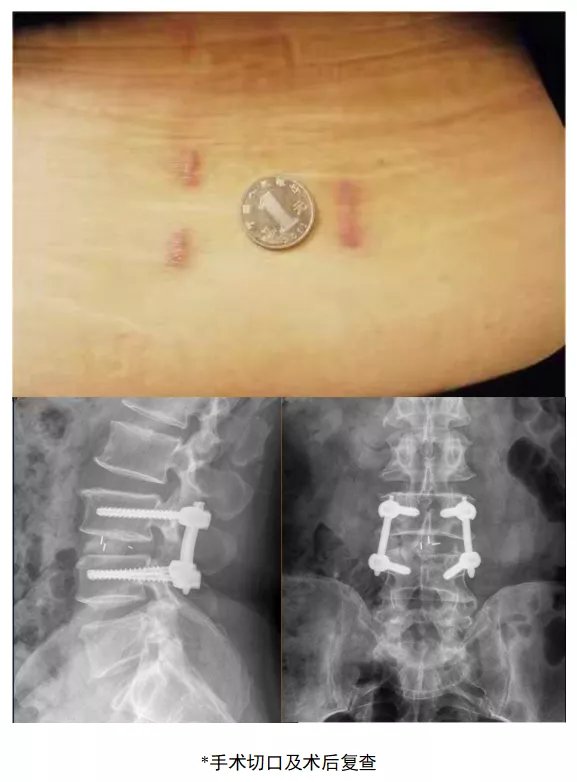

这位来自东北的刘先生是一位老腰椎间盘突出患者了,5年间反复的腰腿痛折磨已使久病成医的他对于保守治疗失去信心,前段时间甚至出现步行50米就腿痛难忍等症状,严重影响患者日常生活。4月中旬,刘先生来到济南市中心医院脊柱外科病区住院治疗,龚维明主任经过详细的体格检查与影像学评估,确诊为腰3-腰4腰椎间盘突出症、腰椎管狭窄症。脊柱外科龚维明医师团队充分分析了患者的病情并制定了诊疗方案,选择了脊柱微创技术——扩张通道系统下经椎间孔入路后路植骨融合内固定微创手术(mis-TLIF),在“硬币”大小的扩张系统下顺利解除患者的腰椎病变,患者术后第二天即下地活动。

手术过程就好比是“管中窥豹”。龚主任解释说:借助微创牵开器,经由肌肉天然的间隙进入,无需广泛切开肌肉韧带等软组织,从而避免了因肌肉软组织剥离过多而导致的迟发性脊柱不稳;通过精准操作,在硬币大小的方寸之间,“庖丁解牛”般地充分松解被椎间盘卡压的神经根,解除患者症状。别看手术伤口不大,手术可以同时做到既减压又融合,是目前可以实现双重治疗效果的脊柱外科微创技术,而手术效果与传统开放手术并无二致。此外,由于手术创伤小,术后患者恢复快,患者可早期下床活动,减少了术后卧床时间,同时减少并发症的发生。这也恰好满足了患者日益增长的健康需求及越来越高的治疗要求。